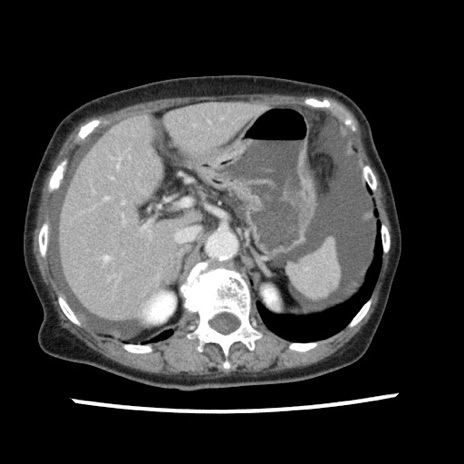

症例1(横断像)

【症例】80歳代女性

【主訴】腹痛

【現病歴】8時間前から腹痛あり来院。

【既往歴】糖尿病、脂質異常症、子宮体癌にて子宮全摘術

【身体所見】意識清明・会話良好だが腹痛で苦悶様、全腹部にわたって反跳痛と圧痛あり

【データ】WBC 13600、CRP 0.14、LDH 224、CK 90